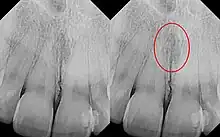

| Identical images with heart-shaped radiolucency highlighted in right film. | |

The nasopalatine duct cyst (NPDC) occurs in the median of the palate, usually anterior to first molars. It often appears between the roots of the maxillary central incisors. Radiographically, it may often appear as a heart-shaped radiolucency. It is usually asymptomatic, but may sometimes produce an elevation in the anterior portion of the palate. It was first described by Meyer in 1914.[1]

As a cyst, the nasopalatine duct cyst requires histological analysis for a definitive diagnosis. Radiographically, the nasopalatine cyst appears as a well-demarcated round, ovoid, or heart-shaped structure presenting in the midline of the maxilla.[6]